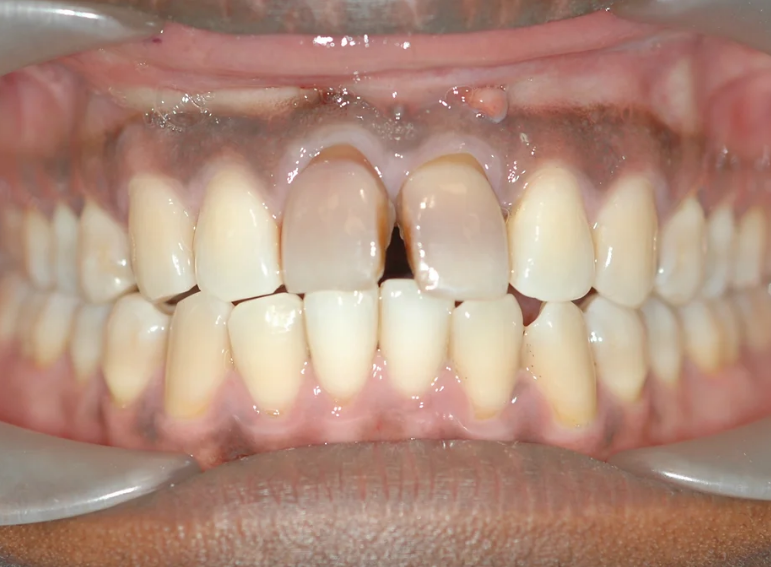

Internal and external whitening of a discoloured central incisor.